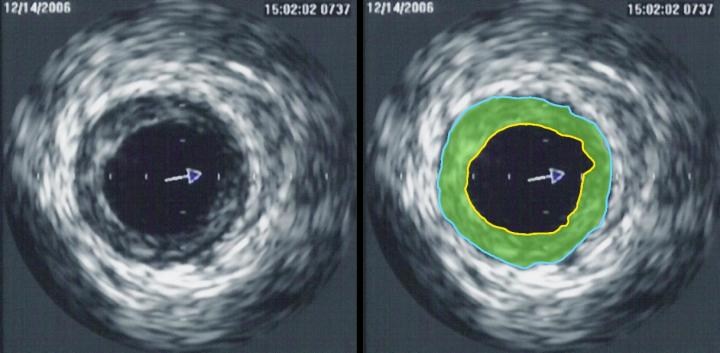

The initial manifestation of the cardiac ischemia is usually the acute coronary syndrome (ACS). Intravascular thrombosis occurs on a damaged atherosclerotic plaque, which leads to the myocardial infarction (MI). The average stenosis of the infarct-related artery is about 48% (which means, the plaque blocks 48% of the vessel diameter). For that reason the patients with small vulnerable plaques may not suffer from a heart pain or other ischemic symptoms, thought to be at high risk of acute myocardial infarction. In cases when an atherosclerosis plaque and the cardia? ischemia are developing gradually, the stable angina pectoris appears as the first sign of the disease.